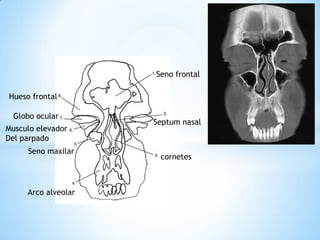

Seno frontal

Globo ocular

Musculo elevador del parpado

Seno maxilar

Arco alveolar

Cornetes

Hueso frontal

Septum nasal